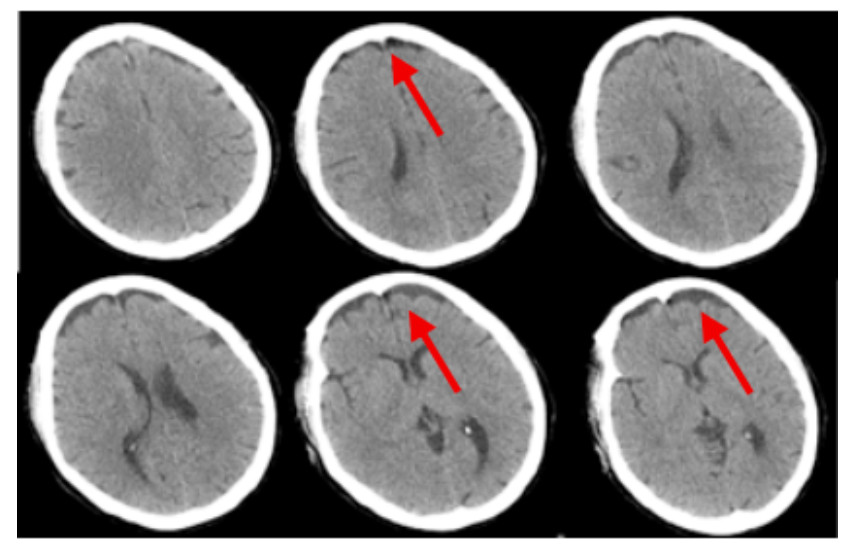

2 结果入院时实验室查急诊血清胆碱酯酶(cholinesterase, ChE):小于196 U/L。血常规:白细胞(white blood cell, WBC)9.24×109/L,中性粒细胞百分比(neutrophil, NEUT%)88.3%,PLT 230×109 /L,红细胞(red blood cell, RBC) 4.08×109/L血红蛋白(hemoglobin, Hb)128 g/L。动脉血气分析:酸碱度(potential of hydrogen, pH)7.247,二氧化碳分压(partial pressure of carbon dioxide, PCO2)30.2 mmHg,氧分压(partial pressure of oxygen, PaO2)93.8 mmHg(呼吸机辅助通气下吸氧浓度为50%),氧合指数284.3%,血钠(Na+) 141.1 mmol/L,血钾(K+) 3.25 mmol/L,乳酸(lactic acid, Lac)8.35 mmol/L,血糖16.05 mmol/L,碳酸氢根12.8 mmol/L,碱剩余-13.2 mmol/L。床旁快速心肌酶:心脏特异性肌钙蛋白Ⅰ(cardiac troponin, cTnⅠ)0.17 ng/mL,肌红蛋白(myoglobin, Myo)123.6 ng/mL,肌酸激酶同工酶(creatine kinase, myocardial-type, CK-MB)17.83 ng/mL。床旁NT-proBNP: 106 ng/L,肝功能:天门冬氨酸氨基转移酶(aspartate aminotransferase, AST)162 U/L,丙氨酸氨基转移酶(alanine aminotransferase, ALT)86 U/L,肌酸激酶196 U/L,乳酸脱氢酶(lactate dehydrogenase, LDH)302 U/L。肾功能:肌酐(creatinine, CREA)104 μmol/L,尿素氮4.84 mmol/L。凝血常规:PT 12.9 s,APTT 34.7 s。新冠病毒抗体阴性。急性感染三项:白介素6 1 148.0 pg/mL,降钙素原(procalcitonin, PCT)0.688 ng/mL,超敏C反应蛋白0.78 mg/L。后期上述指标变化见图 1。床旁胸片显示,(1)双肺纹理增多、增粗、模糊,双肺感染可能;(2)左侧胸腔少量积液可能。见图 2。住院期间讨论CT示:硬膜下积液,见图 3。

| 注:2022-07-21头颅CT示硬膜下积液,如红色箭头所示 图 3 患者住院期间头颅CT结果 |